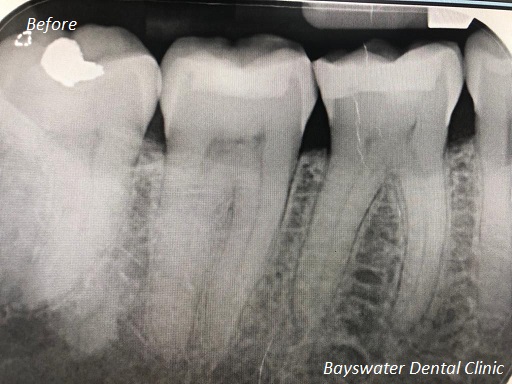

Some root canal treatments which were performed at Bayswater Dental Clinic!

before

after

Root Canal Treatment on a molar teeth which had deep decay!